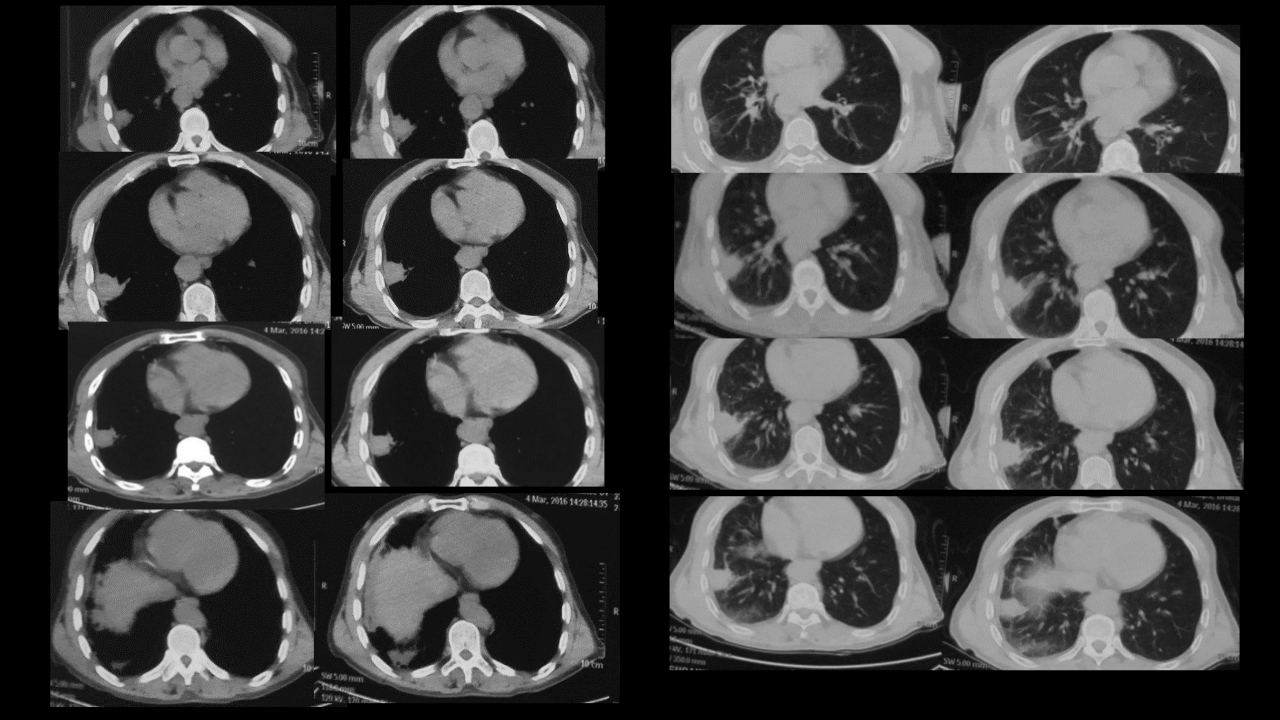

肺部肿块有效的影像检查选择